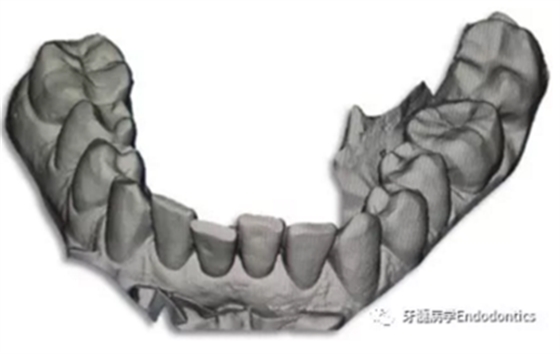

31、41叩痛明顯,牙冠變色(圖1)。溫度和牙髓電活力測(cè)試無反應(yīng)。兩張從不同角度拍攝的x線片顯示,相對(duì)于側(cè)切牙,雙側(cè)下中切牙都有嚴(yán)重的根管鈣化(圖2)。41有明顯根尖周暗影,31根尖周暗影不明顯。為進(jìn)一步證實(shí)31是否存在根尖周病變,同時(shí)精細(xì)觀察31、41的復(fù)雜結(jié)構(gòu),根據(jù)歐洲牙髓病學(xué)會(huì)CBCT應(yīng)用指南(2014),對(duì)患牙拍攝小視野、高分辨率CBCT。CBCT影像證實(shí)31、41均伴有根尖周炎和嚴(yán)重的根管鈣化(圖3)。距離根尖4mm可見根管影像。 由于患牙根管解剖結(jié)構(gòu)較為復(fù)雜,筆者決定使用特殊設(shè)計(jì)的微型鉆頭(直徑0.85mm)進(jìn)行“數(shù)字化導(dǎo)航牙髓治療”。 因此對(duì)下頜進(jìn)行口內(nèi)掃描(圖4)。用coDiagnostixTM軟件(Dental Wings Inc.,Montreal,Canada)將CBCT和口內(nèi)掃描的數(shù)據(jù)進(jìn)行處理,該軟件主要用于引導(dǎo)種植。通過該軟件對(duì)兩個(gè)掃描圖像進(jìn)行疊加后,虛擬鉆頭尖端沿牙長軸對(duì)準(zhǔn)根管下段可見部分(圖5)。三維檢查虛擬鉆的正確位置。

圖4.下頜牙口內(nèi)表面掃描的表面鑲嵌語言(stl-)數(shù)據(jù)。